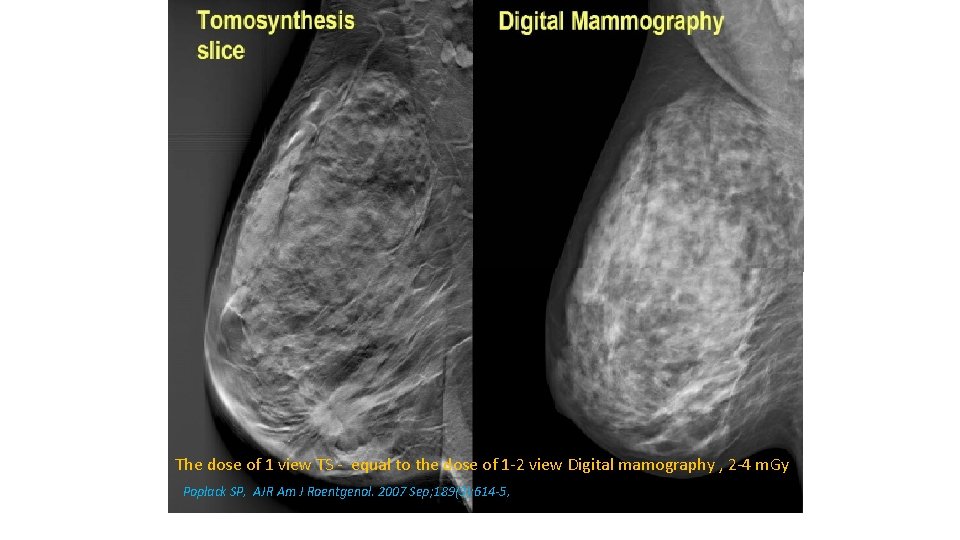

The dose of 1 view TS - equal to the dose of 1 -2 view Digital mamography , 2 -4 m. Gy Poplack SP, AJR Am J Roentgenol. 2007 Sep; 189(3): 614 -5,

Tomosynthesis in Increasing PPV • Dense breast • Architectural distortion detection • Circumscribed masses – margins evaluation